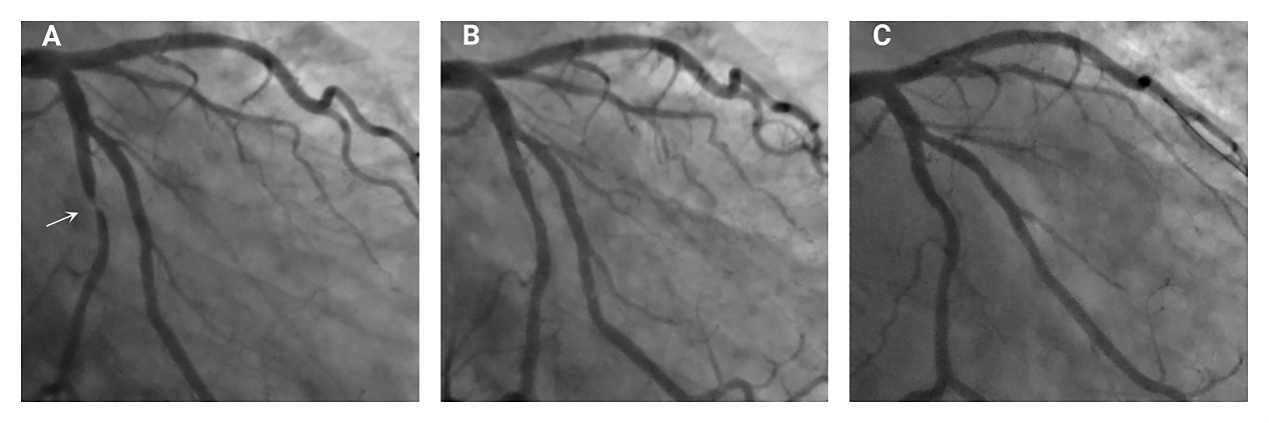

图2. 某患者术前(A),药物球囊术后即刻(B)和7个月随访(C)的冠状动脉造影和OCT检查对应结果

共有52名患者成功接受了DCB治疗。中位随访时间为7个月,靶病变失败的发生率为7.5%。DCB术后,43名患者接受了随访的冠脉造影和OCT检查。QCA显示,晚期管腔丢失为-0.79 ± 0.28 mm。OCT显示,79.1%的病变出现了管腔扩大,65.1%病变夹层愈合。经过多因素分析发现B型夹层(OR 2.92,95% CI 1.34~7.41,P= 0.037)是LLE的预测因素,但脂质斑块(OR 0.09,95% CI 0.01-0.63,P= 0.015)是LLE的危险因素。